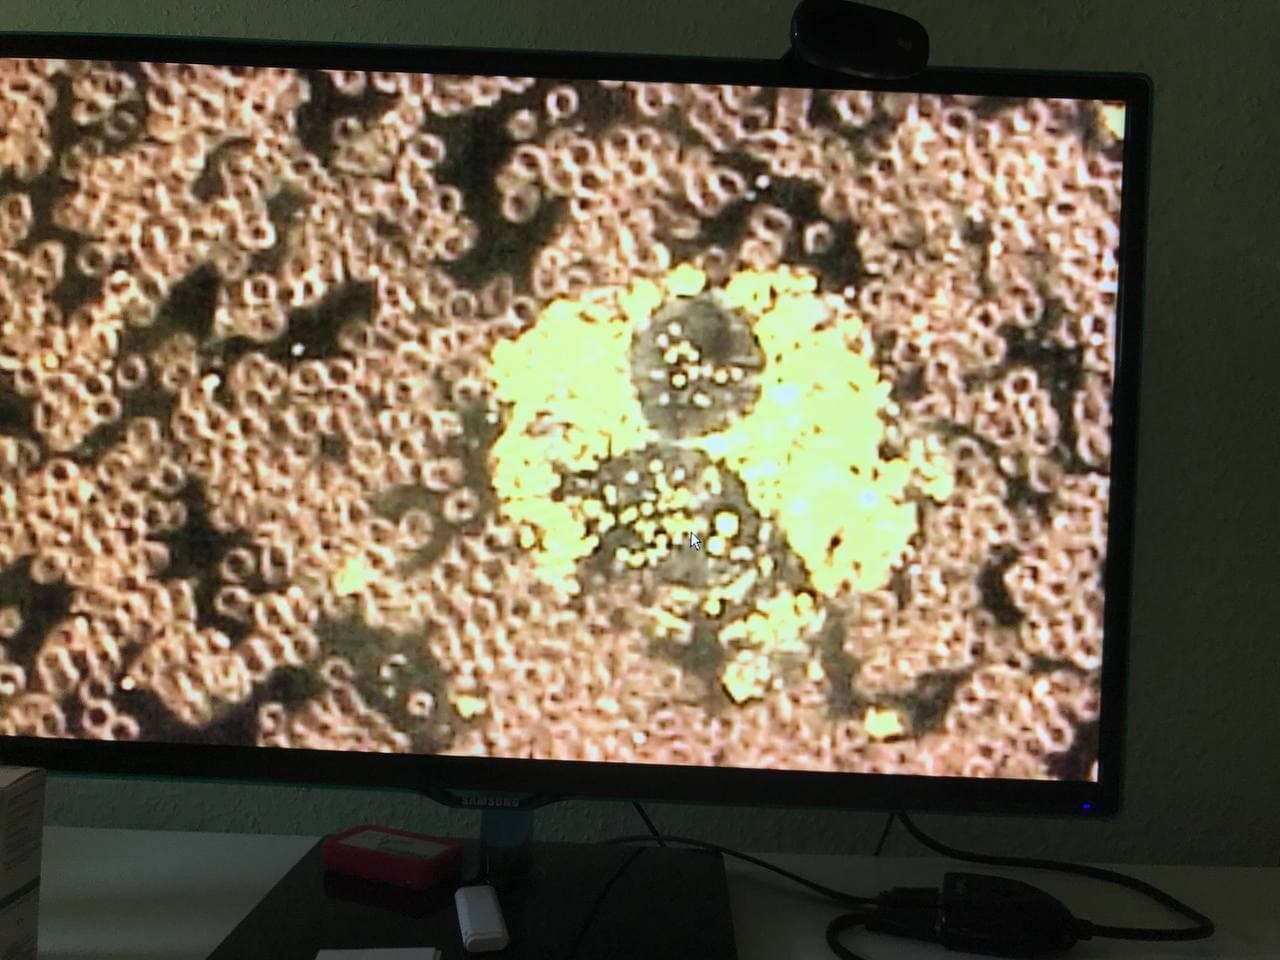

GENgeimpfte Menschen mit schweren

Nebenwirkungen in Südafrika 6.10.2021: Gestapelte

Blutzellen und schwarze Strukturen im Blut - Ärztin Zandre

Botha:

Purer Horror: Arzt entdeckt mysteriöse „schwarze

Strukturen“ im Blut von geimpften Patienten

https://uncutnews.ch/purer-horror-arzt-entdeckt-mysterioese-schwarze-strukturen-im-blut-von-geimpften-patienten/

Video auf Rumble (4.Okt.2021): https://rumble.com/vnbgal-never-before-seen-blood-doctor-reveals-horrific-findings-after-examining-vi.html

Video auf Bitchute (6.Okt.2021): https://www.bitchute.com/video/Sffxfn2Q7RGA/

Video auf VK (7.Okt. 2021): https://vk.com/video472868156_456239639

Video auf GloriaTV (5.Okt.2021): https://gloria.tv/post/CYb3Qraejiiy2SRLNkusqEjaC

Immer mehr Patienten der südafrikanischen Ärztin Zandre

Botha leiden nach der Corona-Impfung unter

Nebenwirkungen. Dazu gehören Thrombosen, Embolien,

kognitive Probleme, Nervenschmerzen und Kurzatmigkeit.

Sie beschloss, das Blut ihrer Patienten unter dem

Mikroskop zu untersuchen und war schockiert.

Die roten Blutkörperchen der Geimpften seien bis zur

Unkenntlichkeit deformiert, sagte Dr. Botha in der Stew

Peters Show. „Das habe ich noch nie gesehen. Ich war

schockiert“, sagte die Ärztin, die seit 15 Jahren in

diesem Bereich tätig ist.

Schwarze Strukturen

Außerdem fand sie bei allen geimpften Patienten mit

Symptomen „schwarze Strukturen“ im Blut. „Ich war sehr

schockiert“, sagte sie.

Botha gelang es auch, einen Janssen-Impfstoff in die

Hände zu bekommen und dessen Inhalt unter dem Mikroskop zu

untersuchen. „Ich war sehr schockiert, denn was ich im

Blut meiner Patienten fand, war auch im Impfstoff

enthalten“, sagte sie. Sie bezog sich auf die schwarze

Substanz, die aus zahlreichen Scheiben mit Löchern

besteht.

Der Arzt entdeckte auch seltsame rechteckige Strukturen

in dem Impfstoff. „Ich weine, wenn ich solche Dinge sehe.

Ich weine, wenn diese Patienten reinkommen“. Sie sagte,

einer ihrer Patienten habe innerhalb von fünf Stunden nach

der Impfung acht Herzinfarkte erlitten und liege nun auf

der Intensivstation. „Ich hoffe, ich kann ihm helfen.“

Letzte Woche wurde der Beipackzettel für den Impfstoff

Corona von Janssen um den Hinweis auf eine venöse

Thrombose, ein Blutgerinnsel in einer Vene, ergänzt.

Dr. Zandre Botha in Südafrika entdeckt das zerstörte Blut

der GENgeimpften mit schweren Symptomen und schwarzen

Objekten drin [17]

Südafrika: Ärztin Zandre Botha: Hier sind intakte

Blutzellen wie Billardkugeln [13] - Südafrika: Ärztin

Zandre Botha: Blutzellen sind gestapelt und bilden

Thrombosen [14]

Südafrika: Ärztin Zandre Botha: Schwarzes Objekt wie eine

Schildkröte im Blut [15] - Südafrika: Ärztin Zandre Botha:

Schwarzes Objekt wie ein schwarzes Wildschwein im Blut

[16]